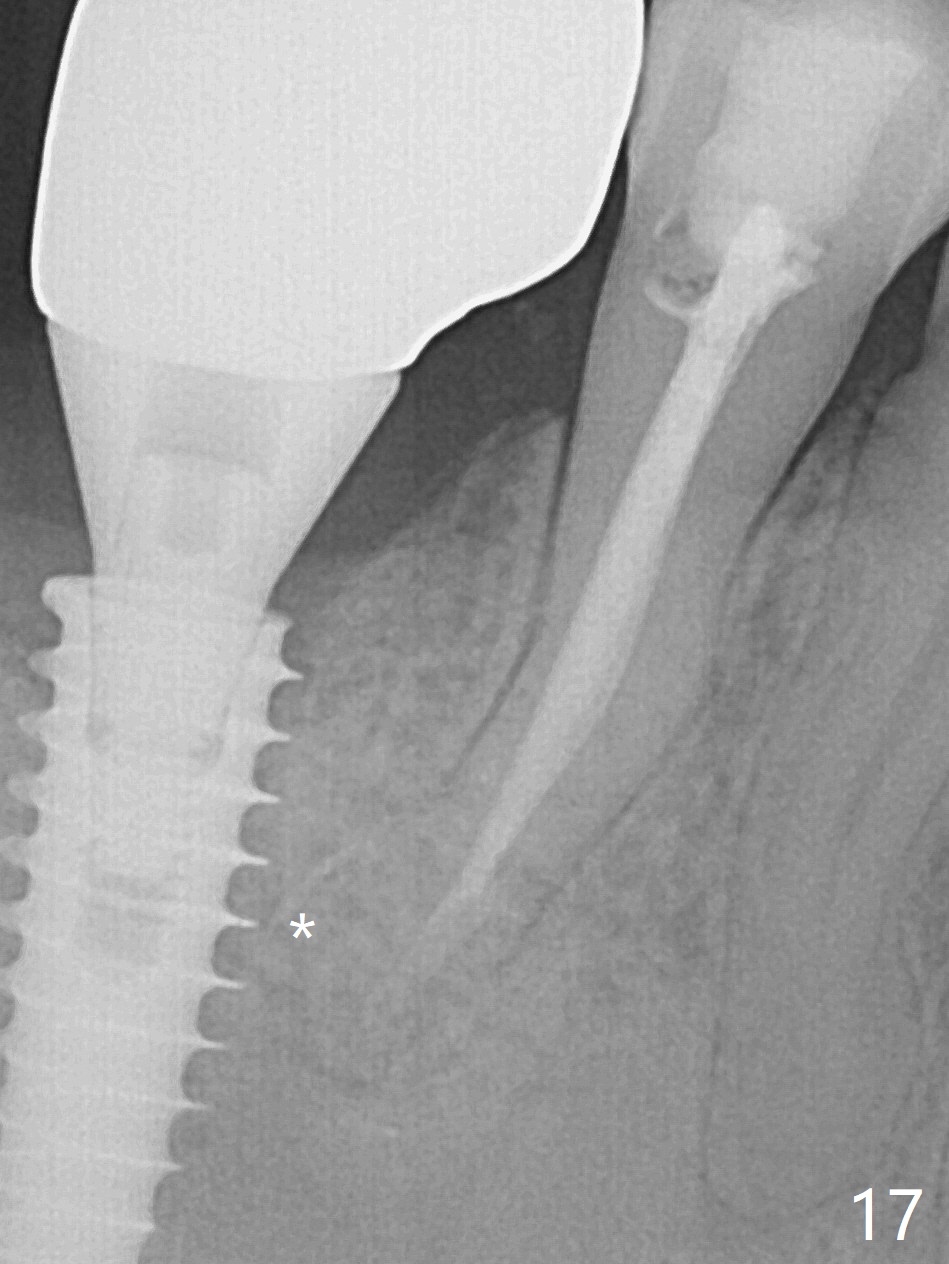

Bone graft seems to sink down and becomes denser 3 months postop (Fig.6 arrow). The bone continues being denser 5 months postop (Fig.7). There is periapical radiolucency of the tooth #29 (^). RCT is done (Fig.8). The pain persists 2 weeks postop (Fig.9,10). There is no missing canal (Fig.9). The apex is close to the implant (Fig.9 *). Apicoectomy will be performed if needed. It appears that the implant is also placed buccal (Fig.10 <) and/or the implant too large for the site. Therefore there should be a 2-3 mm buccal gap before and after implant placement. Separation and reflection of the buccal flap allows better visibility. The pain persists 1 month post RCT and 6 months post implant placement. RCT retreatment is initiated (Fig.11,12) with placement of Calcium Hydroxide paste after redebridement with 30/.04 rotary file at 23.5 mm (.5 mm longer than the earlier RCT, Fig.13). RCT retreatment finishes with apparent transportation and extrusion in 4 weeks (Fig.14,15), followed by apicoetomy (Fig.16,17) (20 days later)). Discomfort remains 2.5 months postop (Fig.18). Keep watching.